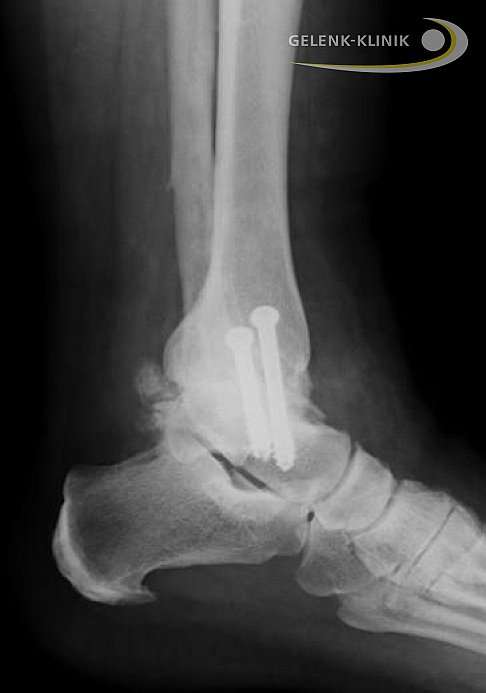

Durch den Erhalt der hinteren Gelenkkapsel ist die Arthrodese bei Belastung, also beim draufstehen, schon ohne weitere Maßnahmen stabil. Die Aufgabe der Schraubenosteosynthese (Knochenverbindung mit Schrauben) besteht darin, das Sprungbein auch bei Nichtbelastung in der richtigen Stellung in der Sprunggelenksgabel zu halten. Durch die Nutzung der Gelenkkapsel als Stabilisator kann die Osteosynthese also mit nur 2 Schrauben erfolgen, die von hinten nach vorne zeigend (in ventraler Richtung) eingebracht werden.

Diese hohe Stabilität ermöglicht gleich nach der Operation eine kräftige Teilbelastung von 30-40 kg.

In der Ansicht von hinten oder vorne ist eine gute Stellung besonders wichtig. Für eine gute Fußfunktion hat sich eine vermehrte Valgusstellung (X-Stellung des Fersenbeines oder Pronation) mit einem leichten Knickfuß im Winkel von 10°-15° bewährt.

Da die Pronationsbewegung besonders wichtig ist und häufig bei einer Arthrose des oberen Sprunggelenks verloren geht, ist der Valgus (X-Stellung) der Ferse besser als eine Varusstellung (O-Stellung), die mit einer vermehrten Belastung des Fußaußenrandes einhergeht.